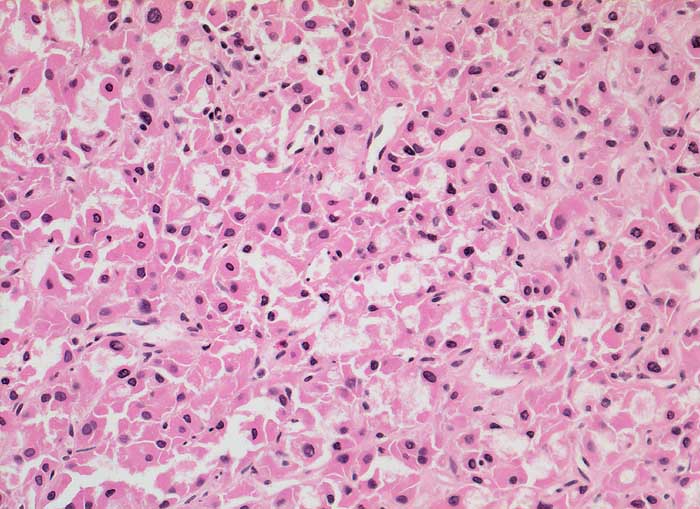

PathoPic ID 5848 - onkozytäres Schilddrüsenkarzinom

onkozytäres Schilddrüsenkarzinom

maligner Tumor

Schilddrüse

Endokrinium

Mikrofollikulärer Tumor aus leicht polymorphen onkozytären Zellen.

Verdacht auf Schilddrüsenkarzinom

Histologie

200